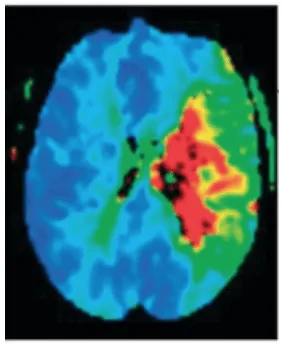

As técnicas de neuroimagem, como a ressonância magnética craniana, permitem confirmar e localizar a topografia da lesão, sendo de grande utilidade no manejo da patologia. Na fase aguda, pode-se determinar o tecido infartado graças às sequências de difusão, bem como quantificar a extensão do tecido por meio das sequências de perfusão (Ustrell-Roig e Serena-Leal, 2007).

A discrepância positiva entre o volume do infarto e o volume da penumbra (mismatch) é utilizada como preditor de boa resposta ao tratamento (um mismatch positivo indica que existe uma grande penumbra em comparação com a área infartada, o que sugere que ainda há tecido cerebral potencialmente salvável). Por isso, é de grande relevância dispor de técnicas de neuroimagem que permitam a delimitação do núcleo do infarto e da zona de penumbra para prever o prognóstico do paciente e utilizá-las ao tomar decisões terapêuticas, selecionando pacientes que possam se beneficiar de tratamentos de reperfusão além das janelas de tempo tradicionais (García et al., 2022) (figura 1).